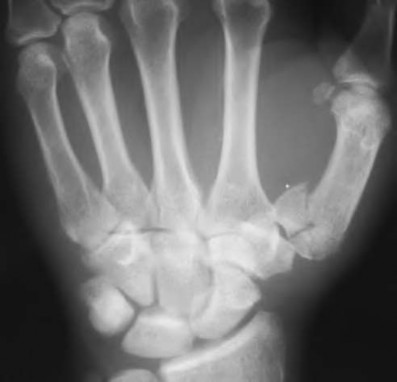

A 35-year-old woman reports wrist pain after a fall onto an outstretched hand. On exam, she has focal tenderness over the wrist snuffbox. A radiograph and CT image are shown in Figures A and B. What is the proper treatment of her injury?